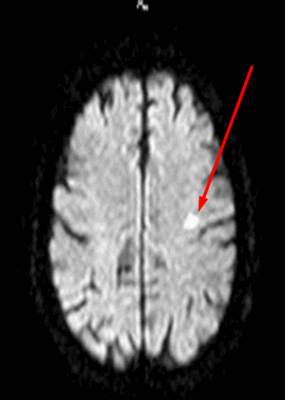

![Абсцесс головного мозга на МРТ]()

Абсцесс головного мозга на МРТ (указан стрелкой)